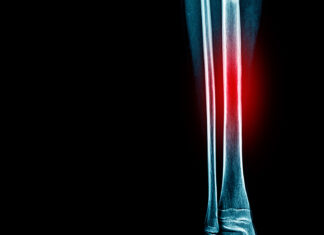

The High-Impact Injury

Stress fractures are one of the five most common running-related injuries and account for six to 14 percent of all injuries sustained by runners....